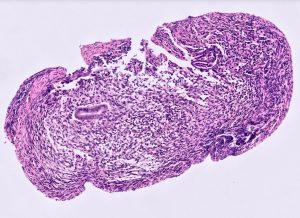

A female patient in her 40s presented with renal impairment. CT intravenous pyelography demonstrated longstanding right hydronephrosis and hydroureter with lower ureteric obstruction. At ureteroscopy there was a lesion in the right lower ureter that was biopsied (three biopsies, each 1mm). This was followed by right distal ureterectomy and ureteric reimplantation. The first four images are from the diagnostic biopsy and the last image is from the resection specimen.

The distal ureterectomy specimen showed endometriosis with similar features to the initial ureteric bioipsy that infiltrated the ureteric muscularis propria and formed a mass undermining unremarkable urothelium. There was no evidience of hyperplasia, atypia or malignancy.